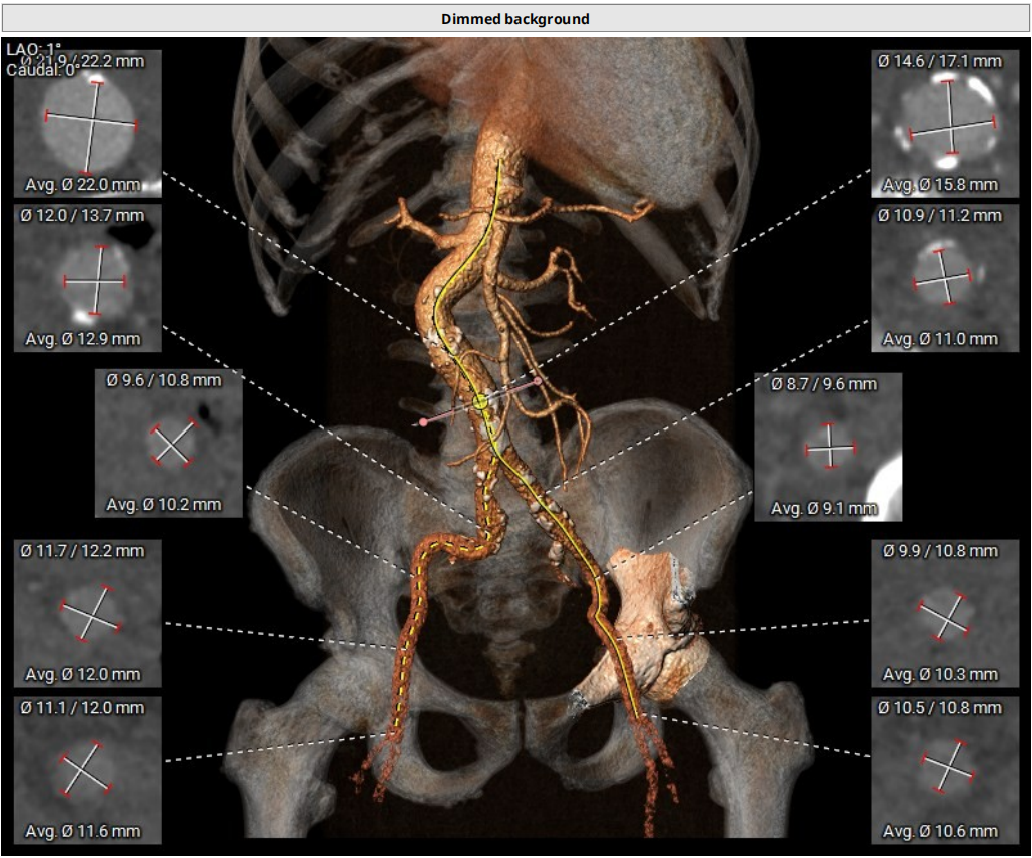

血管入路评估:入路两侧分叉高度适中,穿刺点位置尚可,直径尚可,穿刺点附近未见钙化,右侧最小均径10.2mm,左侧最小均径约9.1mm,16F可扩张鞘能顺利通过;建议右侧为主入路。

血管入路评估:血管穿刺位点直径可,腹主动脉-降主动脉段接近90°迂曲。